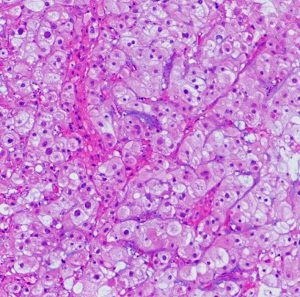

病理像です。軟骨様組織を混在しない純粋な脊索腫です。核を中心にして大きな丸い細胞体には空胞が目立ちます。空胞腫瘍細胞 physaliphorous cellsのシート状配列が特徴的です。左上の写真にわずかに粘液状間質(青く染まるところ)がみえます。